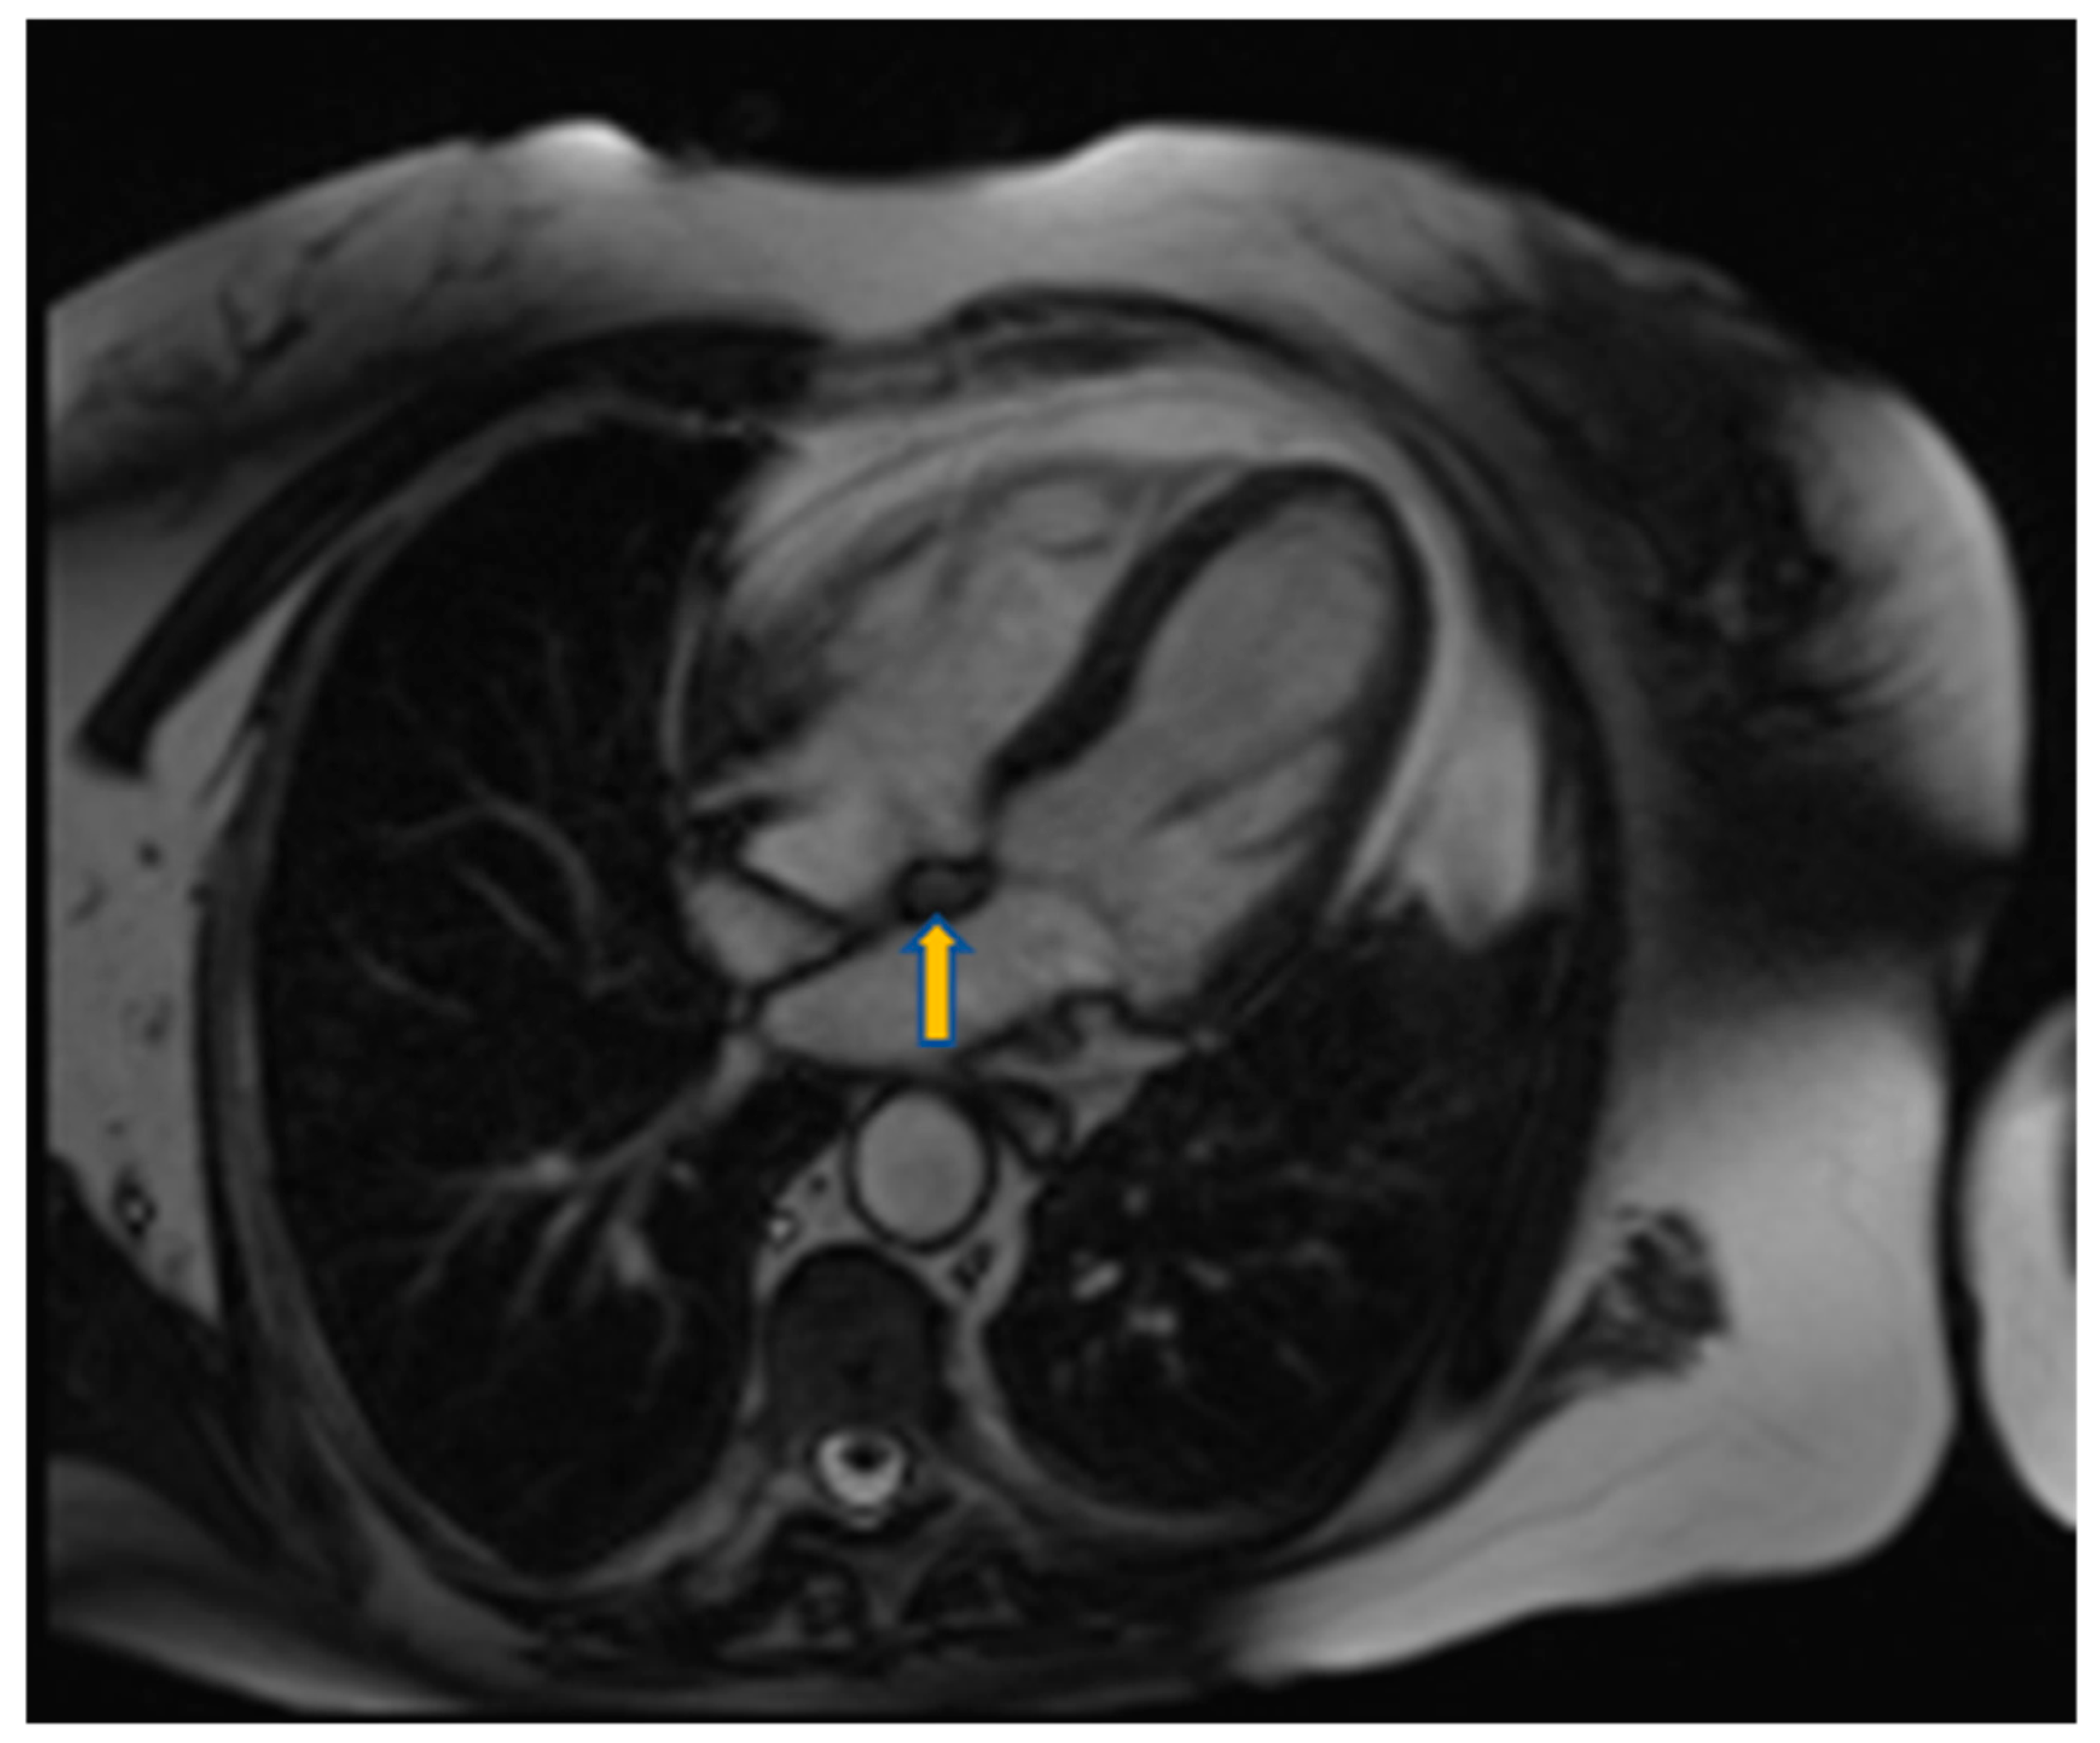

3.4. Cardiac Magnetic Resonance

- Tissue characterization on T1–T2 weighted images:

- T1 hypo/isointensity with high T2 weighted signal intensity characterizes the majority of benign or malignant cardiac tumors

- Apical and hypertrophic cardiomyopathy may mimic cardiac tumors such as fibromas. In such cases fibromas appear hypointense in T2 weighted images while hypertrophic cardiomyopathy hyperintense. Moreover, CMR tagging can highlight the contractile nature of hypertrophic cardiomyopathy [53,54]. High T1 and low T2 weighted signal intensity is indicative of metastatic malignant melanoma.